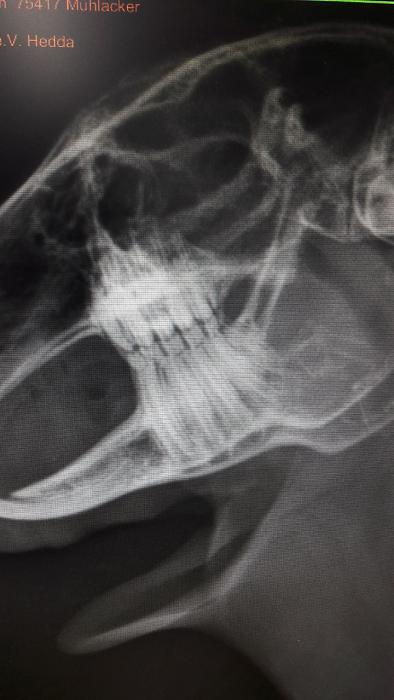

Anbei noch Foto vom TA. Wir haben versucht, das hervorstehende Auge zu fotografieren. Schwierig, wenn alles schwarz drumherum ist ...

Klicke auf die Grafik für eine größere Ansicht

Name:	received_1671701759576773.jpg

Hits:	1

Größe:	39,7 KB

ID:	164548

Name:	received_1671702419576707.jpg

Hits:	0

Größe:	16,2 KB

ID:	164547